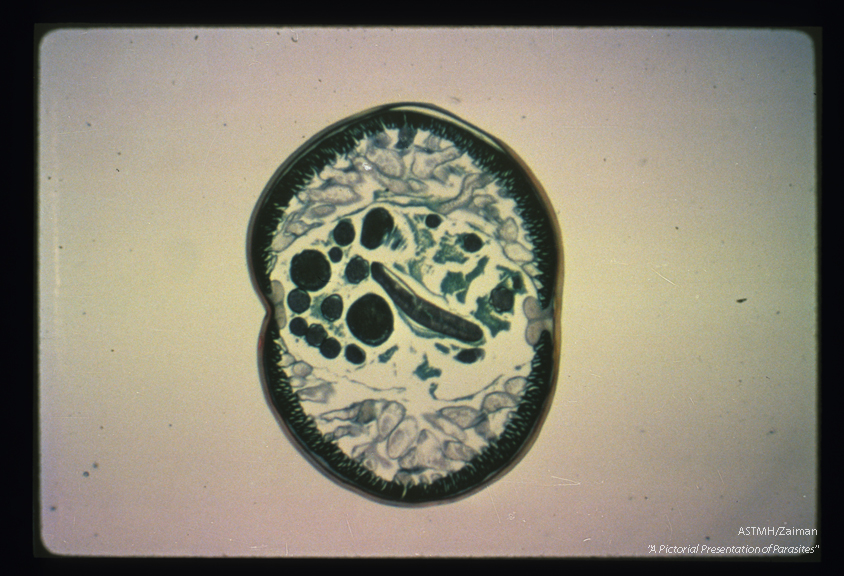

Cross section of an adult male. The male is smaller in cross section. The round ducts are male reproductive structures.

Ascaris lumbricoides

Description: Cross section of an adult male. The male is smaller in cross section. The round ducts are male reproductive structures.